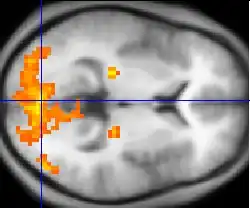

Il s'agit de la capture par une IRM de séquences spécifiques : des séquences echo-planar T2* (ce sont des séquences d'IRM spécifiques) permettant de mettre en évidence le signal BOLD. On obtient ainsi pour chaque voxel une valeur du signal Bold, l'ensemble des voxels correspondant à ce qui est appelé cartes paramétriques. La comparaison statistique des cartes paramétriques seuillées permet de créer des cartes d'activation. Lorsque ces cartes d'activation sont superposées à une IRM cérébrale standard, on obtient l'image classique d'une IRM fonctionnelle (cf l'image en début d'article). L'étude statistique plus poussée de ces cartes d'activation peut permettre de faire de la connectivité fonctionnelle, c'est-à-dire de faire un lien entre différentes zones cérébrales utilisées lors d'une même tâche.